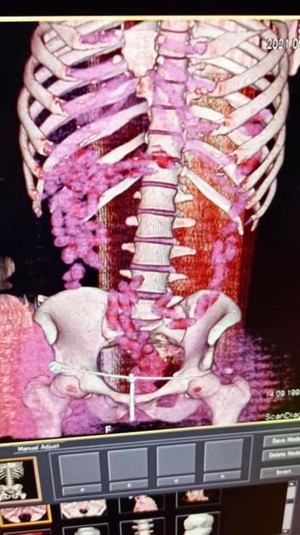

Багатоетапна спецоперація із виявлення зловмисників завершилася у Міжнародному аеропорту «Бориспіль» затриманням двох наркокур’єрів із черговими партіями кокаїну. Один із них приховав «товар» в особистих речах. Інший намагався перевезти через держкордон понад 1 кг кокаїну у кишково-шлунковому тракті. Загалом у ході слідчих дій правоохоронці виявили у наркокур’єрів партію кокаїну загальною вагою 2 кг.